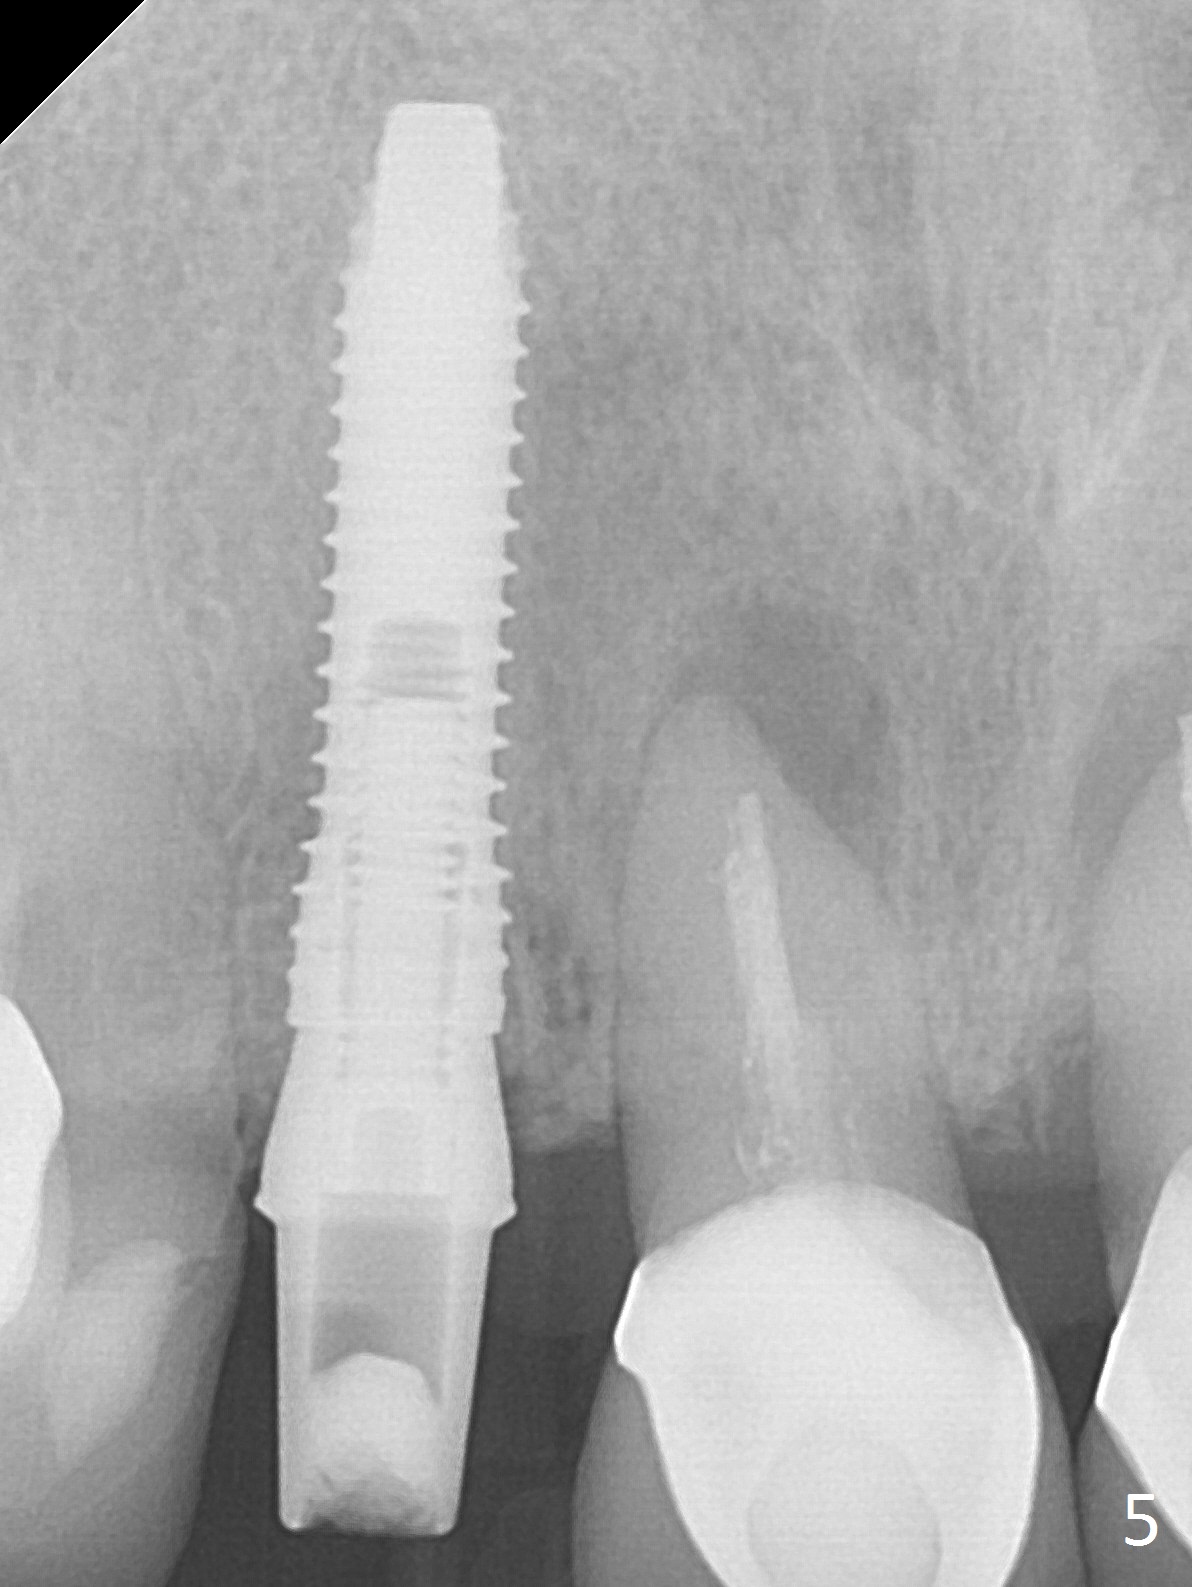

In fact the residual root (Fig.3) is easy to remove. A 3.8x16 mm implant is placed (Fig.4 (with 2 mm buccal gap)) at the level as planned (Fig.2). Insertion torque is acceptable. After placing a 4.5x5(3) mm gold-coated abutment and allograft (Fig.5), an immediate provisional is fabricated (the existing crown is lost). The patient is pleased with the quick, painless procedure.